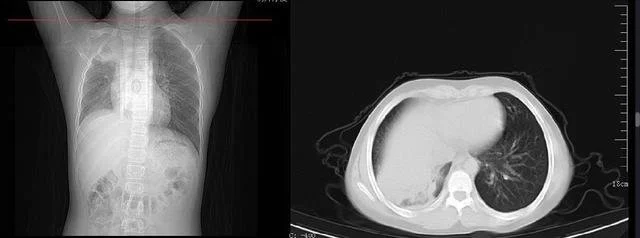

肺部ct顯示,舟舟一側肺部組織大面積變白。

接診的兒科主任張雪榮經過一系列的查體後初步判斷,舟舟已經發展成肺炎了。“收治入院後查胸片顯示,孩子右肺內帶見片狀軟組織樣高密度影,右肺野內亦可見片狀高密度影,右側肋膈角變淺變鈍,膈面模糊。考慮右肺部分不張伴胸腔積液可能。”看到胸片上舟舟的一側肺部組織大面積變白後,家長既自責又後悔。好在經中西醫結合治療後,舟舟目前的症狀已經明顯好轉。